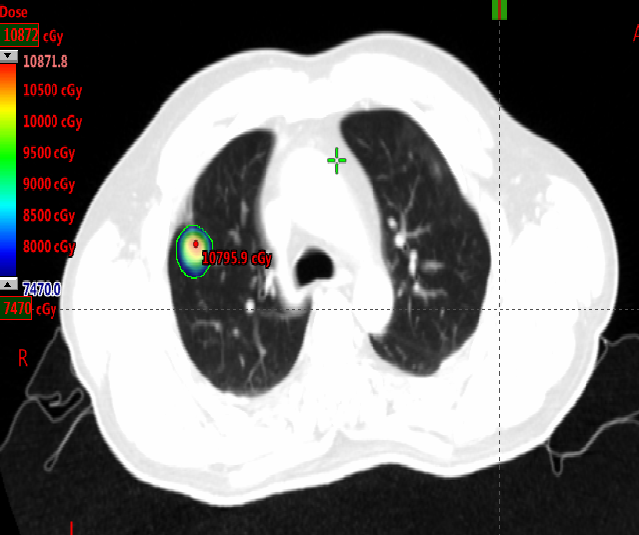

局部治疗(二):SBRT治疗

2020-11-6至2020-11-25 左肺下叶及右肺下叶转移灶放疗:95% PTV1-2 74.7Gy/4.98Gy/15F。

2020-12-31至2021-1-19右肺上叶转移灶放疗:95% PTV 74.7Gy/4.98Gy/15F。

SBRT疗效评价:部分缩小。